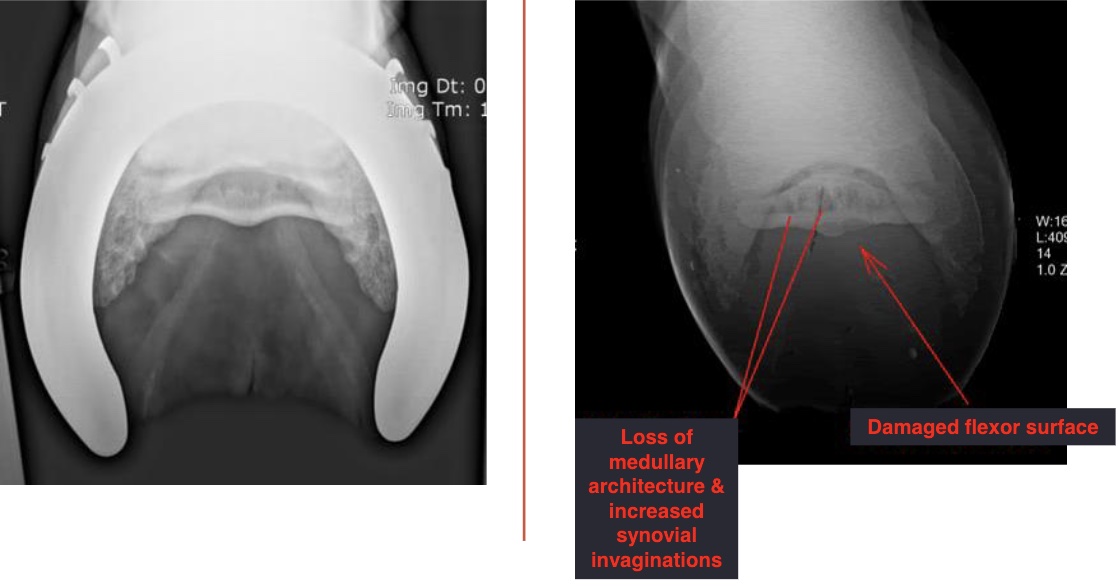

left vs right images

left: normal

right: navicular disease with loss of medullar architecture and increased synovial invaginations (lollipops) and damaged flexor surface (loss of mineralization)

what is this

arrow on left- enthesiophyte (rounded edge)

arrow on bottom- synovial invaginations